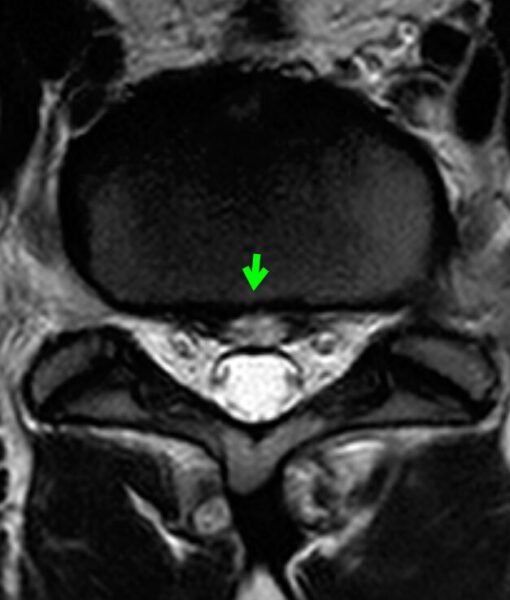

事故から3か月後のMRI

3か月後のMRIでは、

椎間板の信号変化(輝度変化)と、

ヘルニア形態の変化を確認できます。

1回だけのMRIではわからなくても、

時間をおいて比較することで、

事故後の病変の変化を見やすくなります。

〔画像②:事故後3か月MRI〕